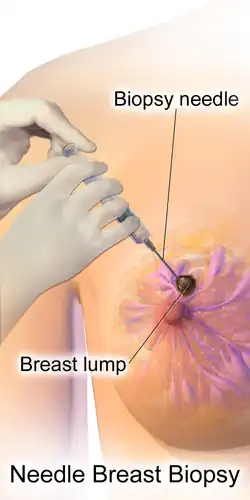

Those who have a suspected tumor from a mammogram or physical exam first undergo additional imaging – typically a second "diagnostic" mammogram and ultrasound – to confirm its presence and location.[22] A biopsy is then taken of the suspected tumor. Breast biopsy is typically done by core needle biopsy, with a hollow needle used to collect tissue from the area of interest.[42] Suspected tumors that appear to be filled with fluid are often instead sampled by fine-needle aspiration.[42][43] Around 10–20% of breast biopsies are positive for cancer.[44] Most biopsied breast masses are instead caused by fibrocystic breast changes, a term that encompasses benign pockets of fluid, cell growth, or fibrous tissue.[44]